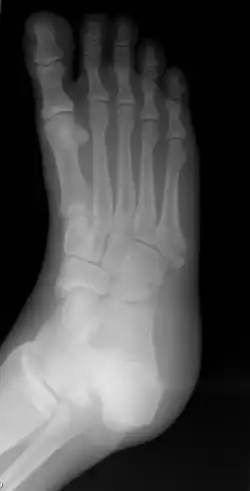

Диагноз ставится после рентгеновского исследования. Для большей точности диагноза рентген делают с разных углов и положений.